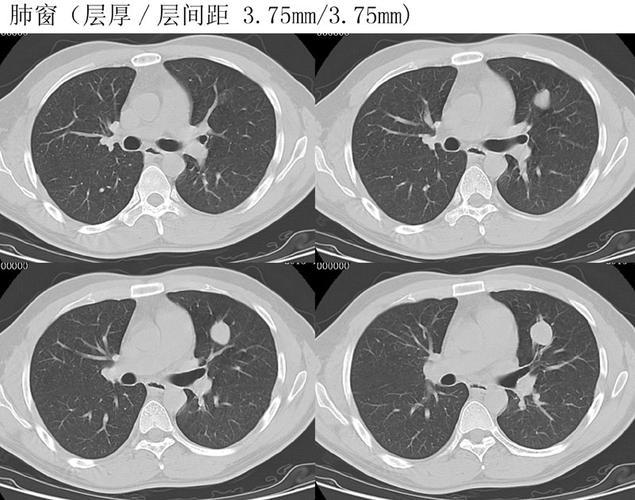

最终行手术切除,病理结果为右肺上叶微浸润性腺癌及原位癌.